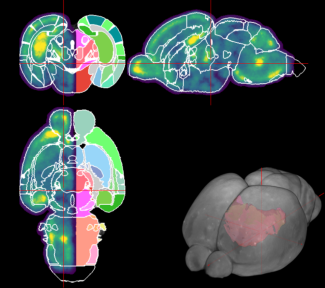

Overview of Lambada's user interface. During the early stages of development, there is a strong correlation between the animal's sensory experience and the formation of blood vessels.

At birth, the brain has a rudimentary vascular network that becomes denser during the first weeks of postnatal life. Credit: Nicolas Renier.